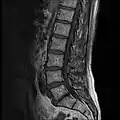

MRI lumbar spine with degeneration (sagittal T2 FRFSE)

MRI lumbar spine with degeneration (sagittal T1 FSE)